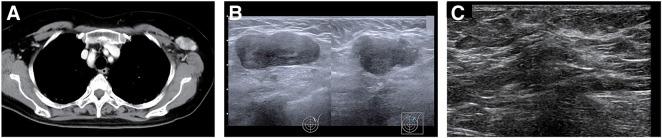

一名63岁女性出现进行性呼吸困难。影像学检查显示双肺弥漫性磨玻璃影和左腋窝淋巴结肿大。血液检查显示KL-6水平和抗MDA5抗体升高。尽管未观察到皮肤病变或肌炎,但她被诊断为抗MDA5抗体阳性相关间质性肺炎。开始进行免疫抑制治疗,包括类固醇冲击治疗、他克莫司、环磷酰胺冲击治疗和血浆置换,肺部状况得到改善。然后她最初被转诊至整形外科,以进一步评估左腋窝肿大淋巴结。左腋窝肿大淋巴结切除活检显示三阴性隐匿性乳腺癌(cTXN1M0,IIA期)。患者转诊至我科后,开始进行NAC,在避免间质性肺炎加重的同时取得了临床部分缓解。完成NAC后,进行了左腋窝淋巴结清扫,最终病理诊断为ypTXN2aM0(IIIA期)。由于存在间质性肺病恶化的风险,术后未进行放疗,给予卡培他滨治疗6个月。治疗后患者已无复发存活3年。